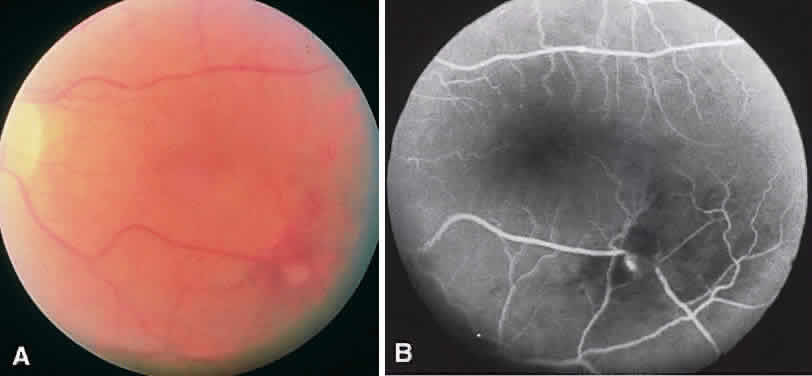

Diabetic macular edema (DME) is a clinical diagnosis made with the slit-lamp biomicroscope. Intraretinal thickening is divided into focal and diffuse forms. Focal retinal edema is usually caused by specific leaking microaneurysms visible as pinpoint areas of leakage on fluorescein angiography (FA). The diffuse form of macular edema, conversely, usually represents a more widespread disruption of the inner blood-retina barrier. FA typically depicts large areas of leakage. It is important to remember that leakage of dye on FA does not always mean intraretinal thickening is present. Diagnosis of macular edema is based on the clinical examination of the retina.